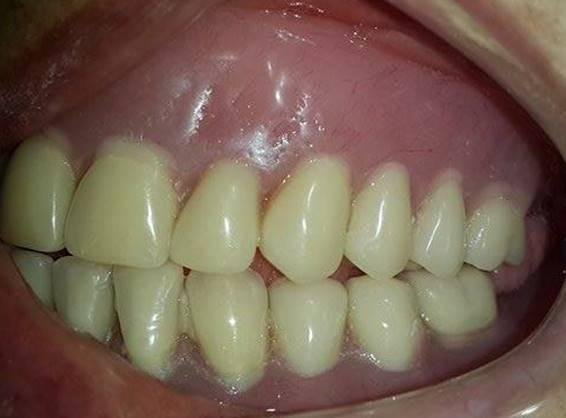

TRATAMIENTO FINAL

Prótesis total superior e inferior elaboradas con Eclipse

EVOLUCIÓN

7 días después

"Me siento mucho mejor, ahora si puedo comer" Paciente